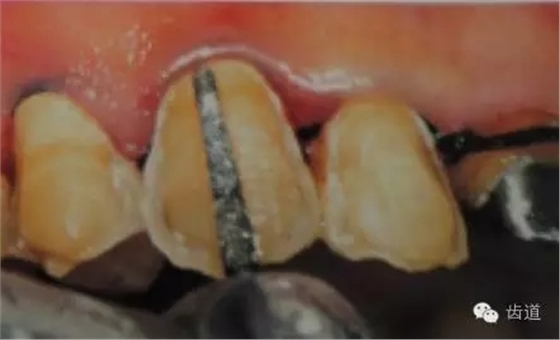

5、齦緣制備:通常瓷貼面的齦端邊緣位于齦上近齦緣處,但當(dāng)美觀要求時(shí)也可以設(shè)計(jì)在齦下0.5mm。

預(yù)備齦下邊緣之前要先排齦,之后選用圓頭錐形車針磨除牙體到所設(shè)計(jì)的邊緣位置。

1)排齦

2)制備